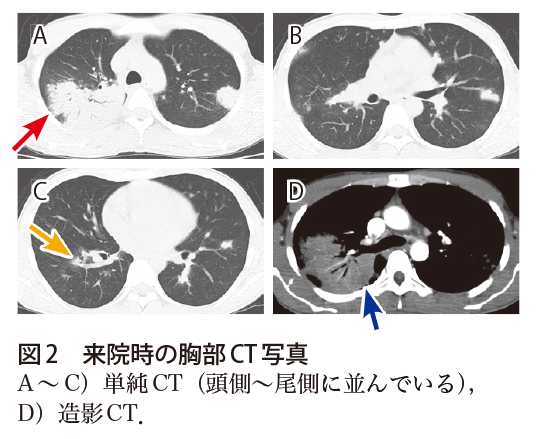

解答 解説 発熱 胸痛 呼吸困難で受診した30歳代男性 実践 画像診断q A 羊土社 レジデントノート 実践 画像診断q A 羊土社 レジデントノート 羊土社